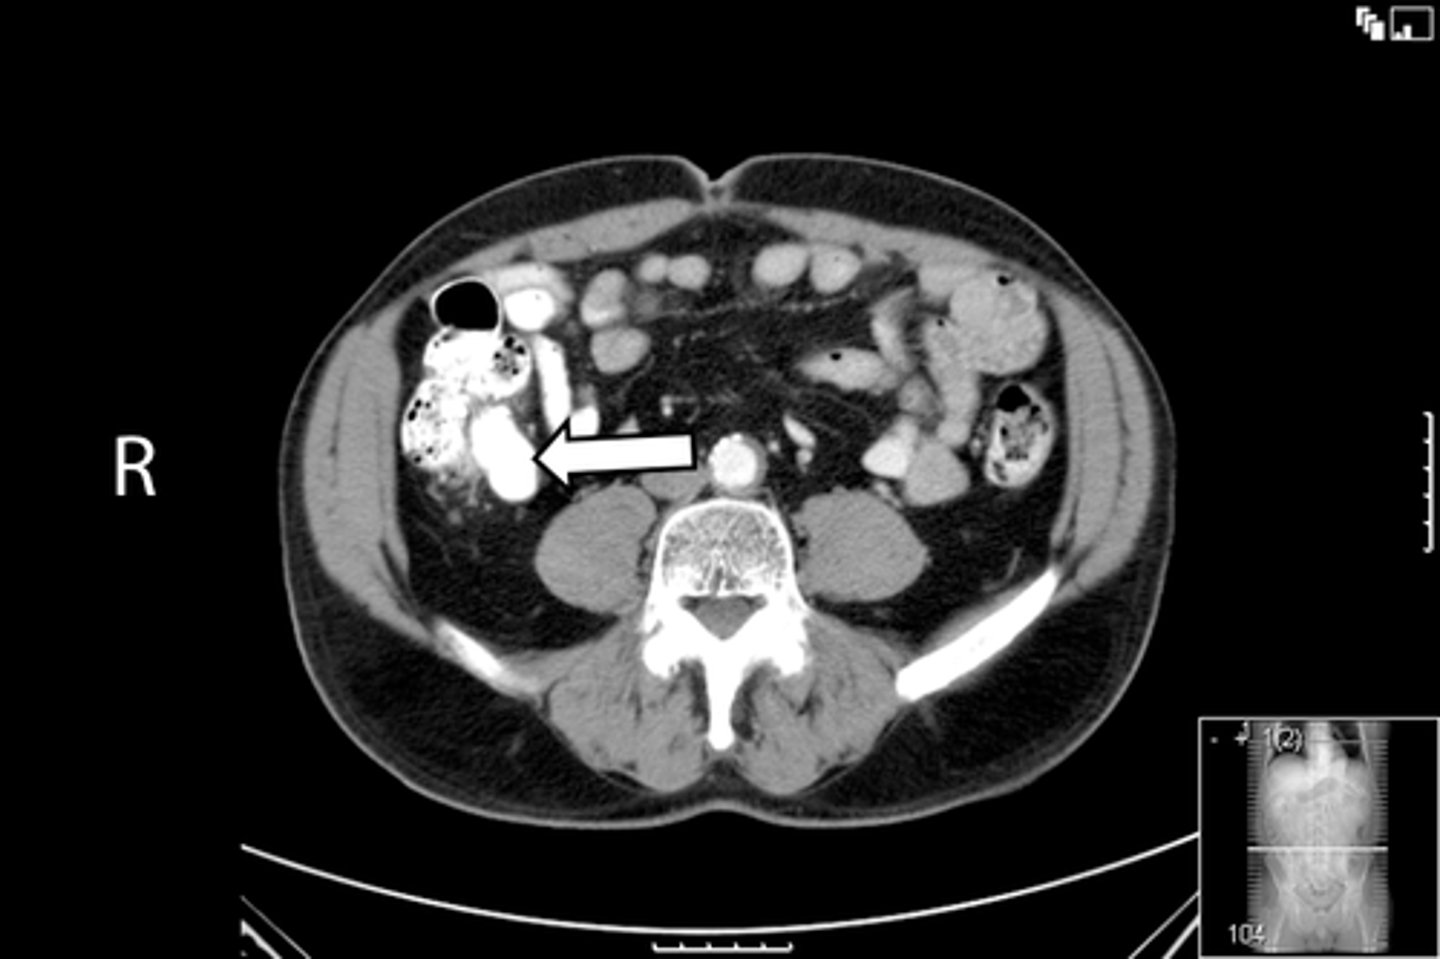

Axial male pelvis CT

What is the image?

<p>What is the image?</p>

55

New cards

Aorta

What is indicated in the image?

<p>What is indicated in the image?</p>

56

Cecum

57

IVC

58

L ilium

59

L psoas muscle

60

R ilium

61

R psoas muscle

62

R rectus abdominis

63

Terminal ilium